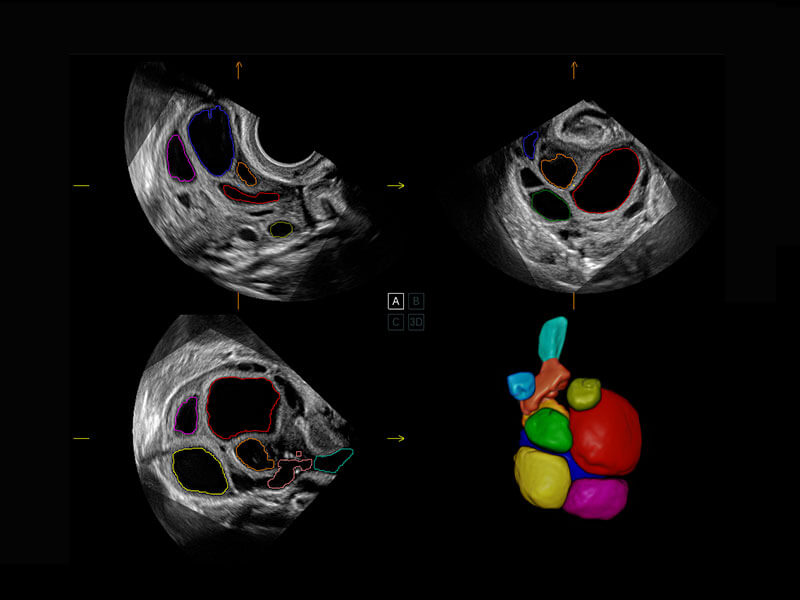

腔内三维-宫内节育器

腔内三维-光影成像